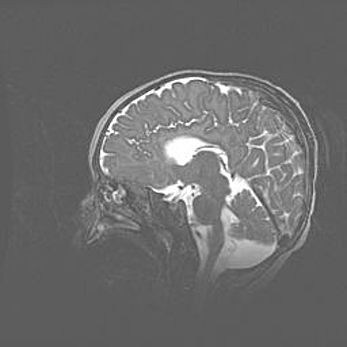

Неполная лизэнцефалия (пахигирия). Открытая гидроцефалия.

Возраст: 17 дней

Вес: 3110 г

Пол: мужской

Окружность головы: 33,5 см

Срок гестации: 35-36 недель

Лизэнцефалия—недоразвитие корковой пластинки и мозговых извилин в результате нарушения миграции нейронов коры. Поверхность мозговых полушарий гладкая. Микроскопически выявляется отсутствие нормальных слоев коры и скопление групп нейронов в подкорковом белом веществе.

Пахигирия—уменьшение числа вторичных извилин. В пораженном полушарии нервные клетки образуют толстый недифференцированный слой с неправильно расположенными нервными волокнами и группами гетеротопных клеток. Нервные клетки незрелые. Белое вещество истончено. При этом нередко аномально развит корково-спинномозговой путь.